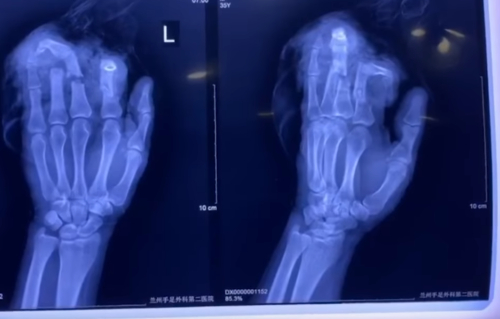

Πάνω στον συζυγικό καυγά ο άνδρας από την Κίνα άρπαξε έναν μπαλτά και μπροστά στα έντρομα μάτια της γυναίκας του έκοψε επιτόπου τέσσερα δάχτυλα από το αριστερό του χέρι!

Οι γιατροί κατάφεραν να κολλήσουν ξανά τα δάχτυλα του άνδρα που πλέον δηλώνει: «Ήξερα ότι δεν έπρεπε να χτυπήσω ή να πληγώσω τη γυναίκα μου. Άρπαξα ότι βρήκα μπρoστά μου και χωρίς να έχω τον έλεγχο έκοψα τα δάχτυλά μου».